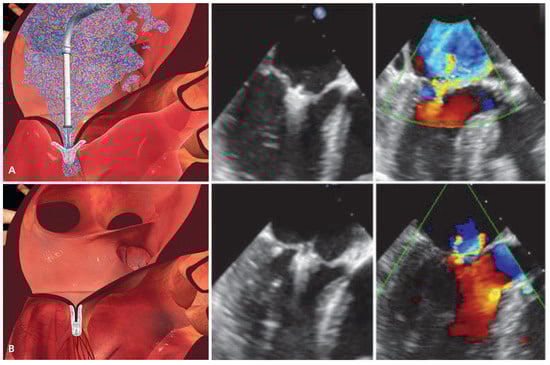

The MitraClip device consists of a percutaneously delivered MRI-compatible cobalt-chromium implant with two arms and two grippers which are used to grasp the opposing edges of the mitral leaflets (Figure 3). The procedure is generally performed under general anaesthesia with fluoroscopic and transoesophageal echocardiographic guidance and haemodynamic monitoring with a Swan-Ganz catheter in the pulmonary artery. The use of X-plane and 3D echocardiography is particularly helpful to visualise mitral valve anatomy and allow orientation of the device in 3D [27]. The device is delivered via transfemoral venous route. After transseptal puncture, the transseptal sheath is exchanged by a steerable 24-F guide catheter (which tapers to 22-F at the interatrial septum) through which the clip delivery system is advanced into the left atrium. Thereafter, the MitraClip device is manoeuvered under echocardiographic guidance, aligned with the origin of the regurgitant jet, and pushed below the level of the mitral leaflets into the left ventricle (LV). Careful consideration must be given to a perpendicular orientation of the clip arms and the leaflet edges before closing the clip (3D echocardiography). After opening the two arms of the clip, the device is retracted with extended arms (Figure 4A) and both leaflets are grasped by closing the grippers. Once adequate leaflet insertion is ascertained with echocardiography, the arms of the Mitra- Clip can be closed to approximate both scallops and restore coaptation. MR is immediately assessed by transoesophageal echocardiography and haemodynamic measurements, and if necessary, the device can be repositioned by reopening the arms and releasing the leaflets. If the desired result is obtained, the MitraClip is deployed and released from the delivery catheter (Figure 4B). Repeat clip insertion can be performed if MR reduction is suboptimal and the result is expected to improve with more than one clip. The only limitation to the number of clips implanted is the development of significant mitral stenosis.

Figure 4. Schematic and echocardiographic images during MitraClip implantation. (A) After transseptal puncture, the MitraClip device is advanced over a steerable transseptal sheath, aligned with the origin of the MR jet and manoeuvered into the left ventricle. Thereafter, the clip is retracted with extended arms in order to grasp both mitral leaflets. The echocardiographic images shows adequate leaflet insertion, the MR jet is still considerable. (B) After closing both arms of the MitraClip device, the edges of the mitral leaflets are approximated thereby restoring coaptation and creating the typical double orifice mitral valve. After confirming adequate MR reduction on echocardiography, the clip is deployed and released from the delivery system. (Images [A, B] courtesy of Abbott Vascular. © 2012 Abbott Laboratories. All rights reserved.).